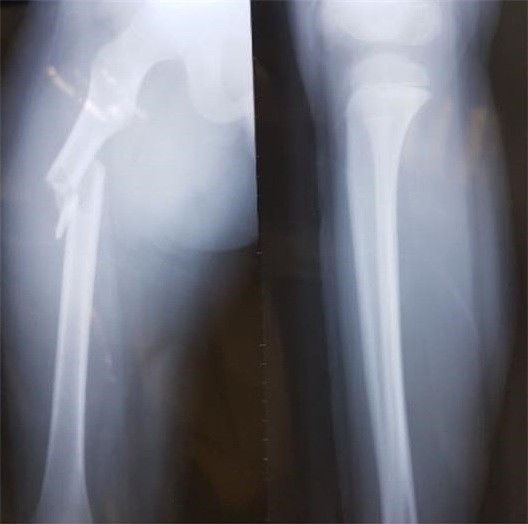

Cùng ngày, cháu được đưa đi cấp cứu tại Bệnh viện Nhi Trung ương. Theo bác sĩ, Kiên bị gãy xương đùi phải nhưng bó bột không thành công vì vết thương quá nặng. Nam sinh được chuyển sang Bệnh viện Việt Đức, Hà Nội. Bác sĩ chỉ định em phải mổ, nẹp vít xương.

Theo bác sĩ, nếu Kiên chỉ chạy chơi trong sân trường, em khó bị gãy xương đùi. Đây là bộ phận cứng, người không có bệnh lý về xương phải bị lực tác động mạnh mới có thể gây tổn thương. Đồng thời, Kiên có vết xước sau hông trái, dự đoán sau khi bị đâm mạnh, cháu ngã ngửa về phía sau.

| Hình ảnh khi xương đùi của học sinh Trần Chí Kiên được chụp X-quang. Ảnh: NVCC. |